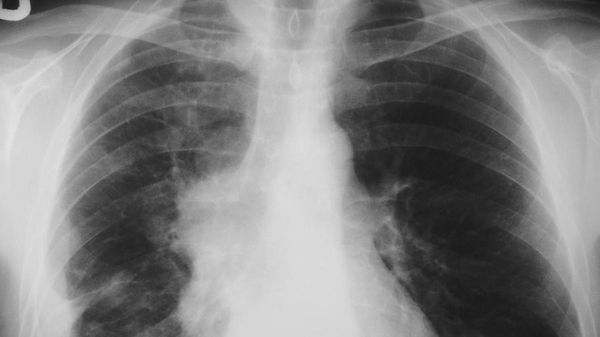

A distanza di dieci anni dall’entrata in vigore la legge anti fumo, meglio conosciuta come legge Sirchia, che vietava il fumo nei locali pubblici, sono stati ottenuti risultati importanti come la diminuzione del 18% della prevalenza dei fumatori (dal 23,8% del 2003 al 19,5% del 2014 secondo i dati ISTAT), la riduzione dei ricoveri per infarto del 5% ogni anno, la diminuzione del 25% delle vendite…